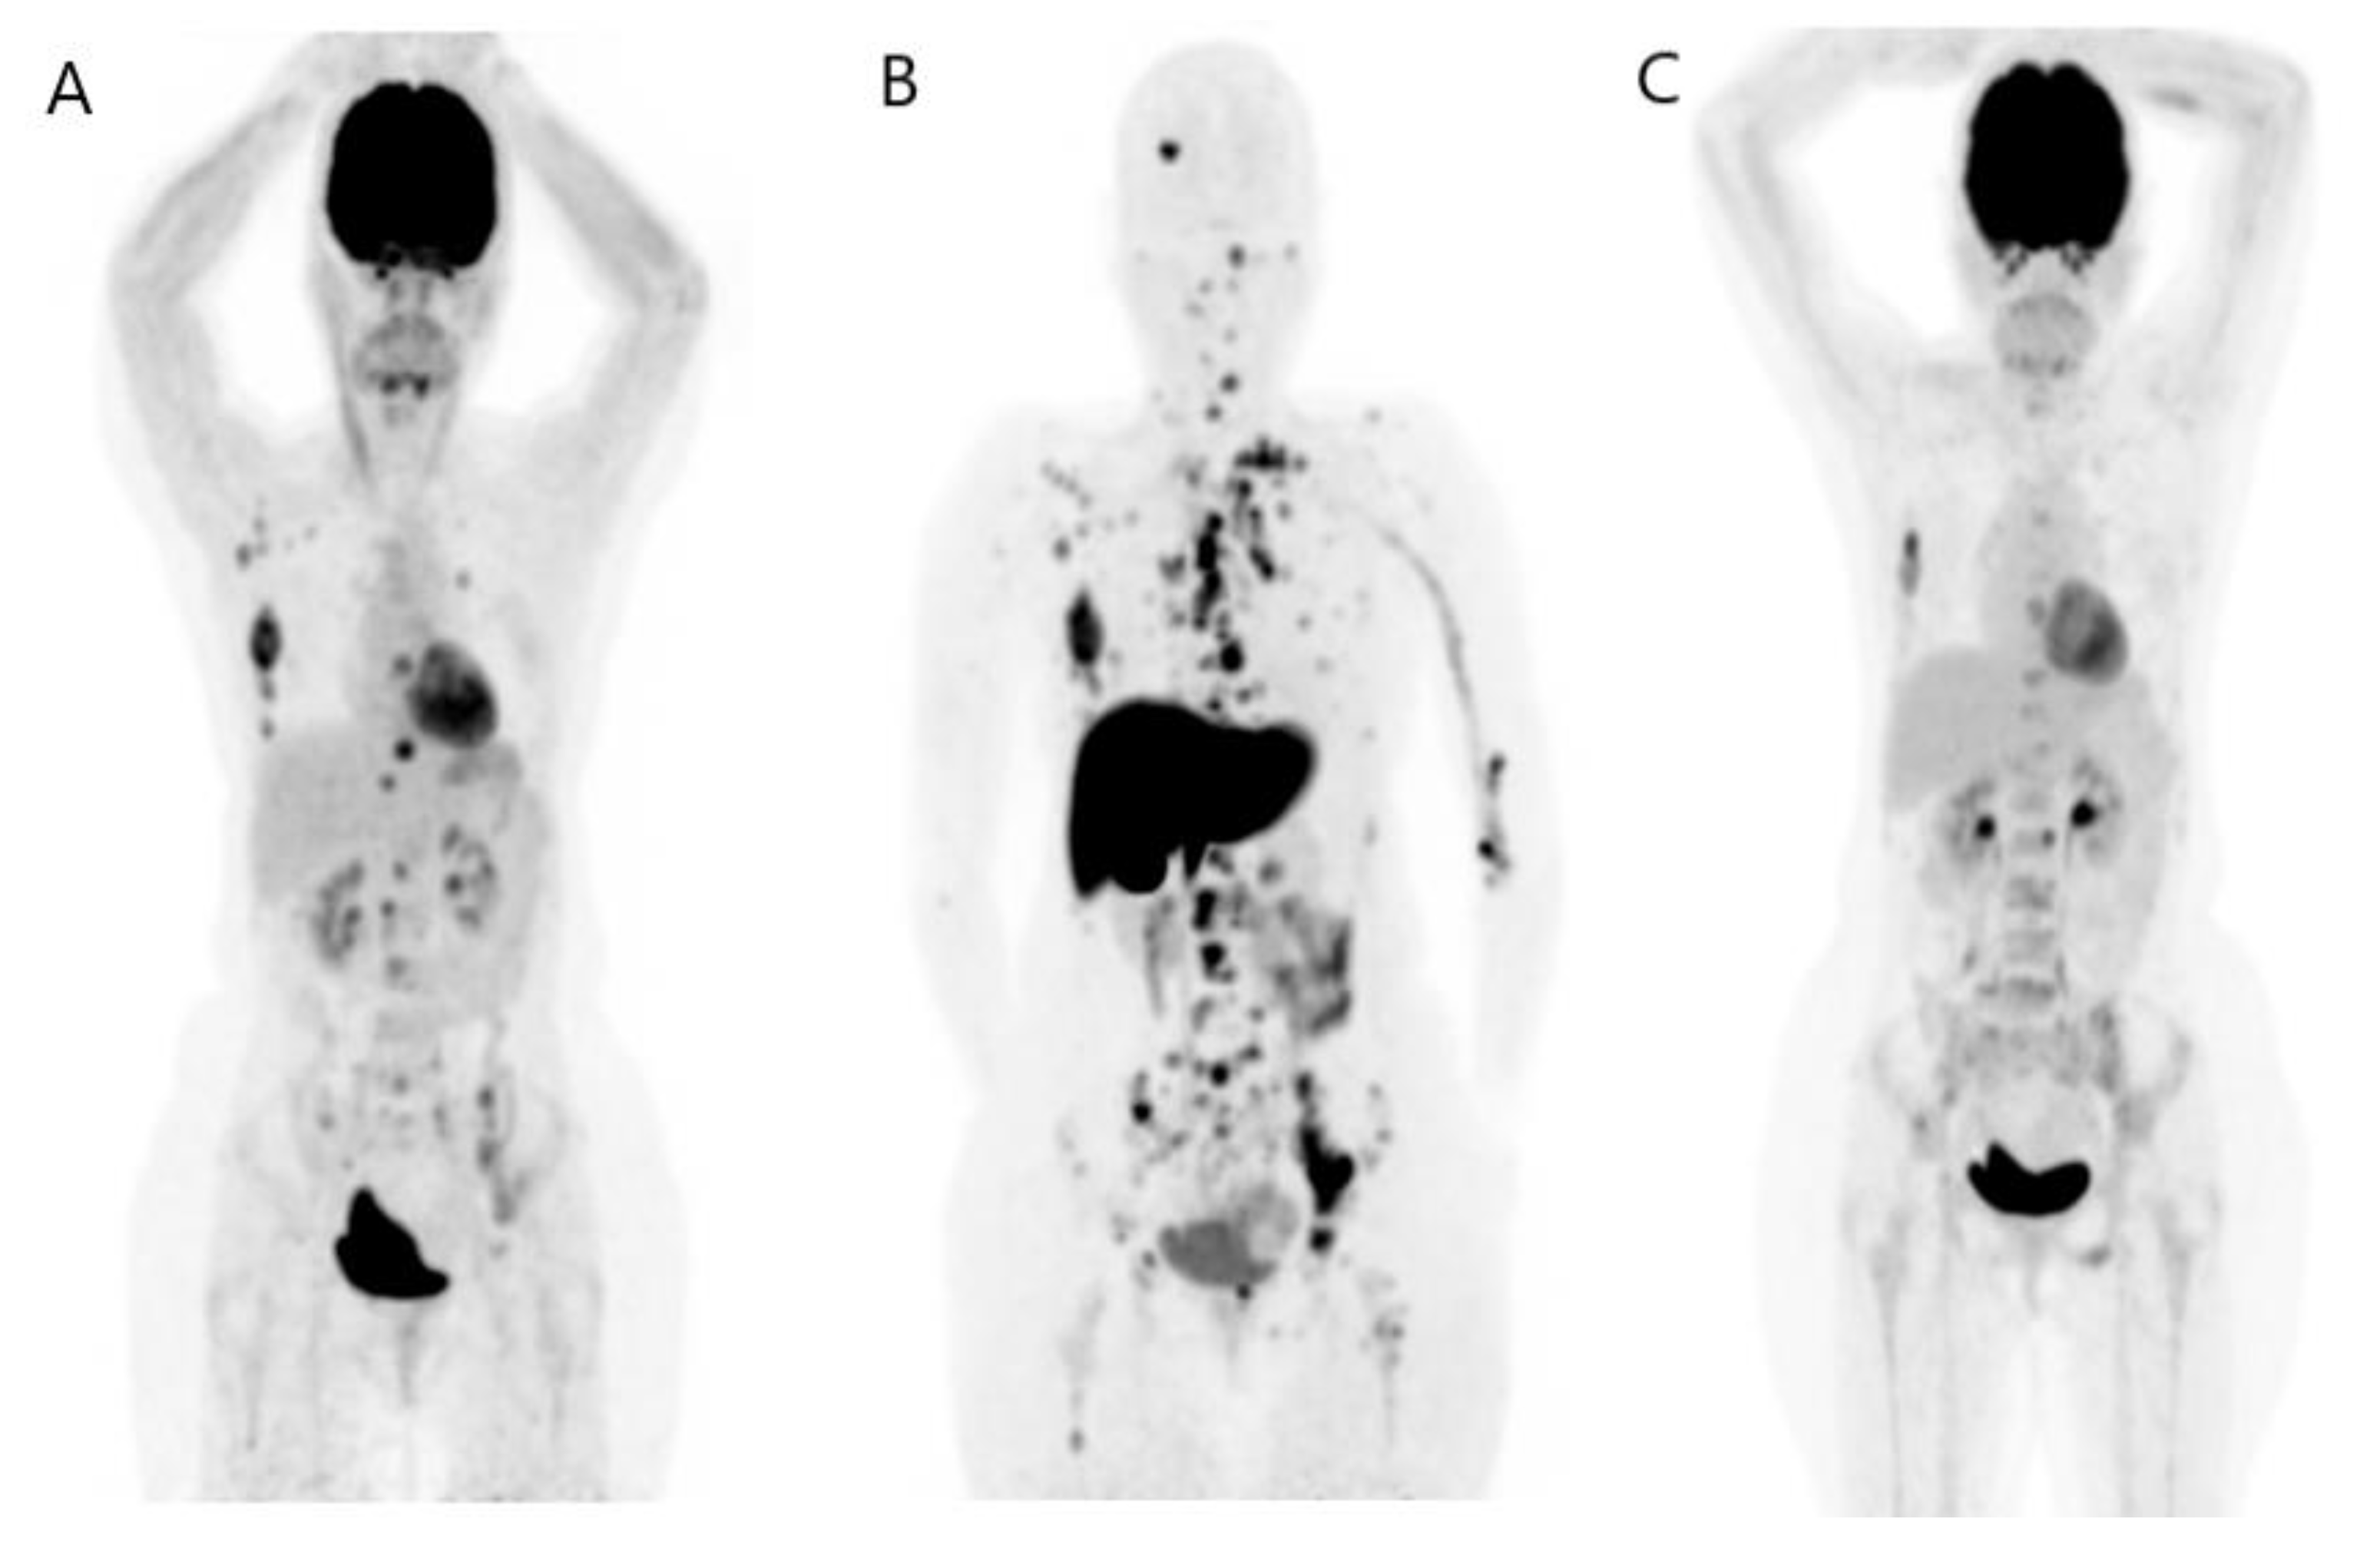

- Kömek, H.; Can, C.; Güzel, Y.; Oruç, Z.; Gündoğan, C.; Yildirim, Ö.A.; Kaplan, İ.; Erdur, E.; Yıldırım, M.S.; Çakabay, B. 68Ga-FAPI-04 PET/CT, a new step in breast cancer imaging: A comparative pilot study with the 18F-FDG PET/CT. Ann. Nucl. Med. 2021, 35, 744–752. [Google Scholar] [CrossRef]